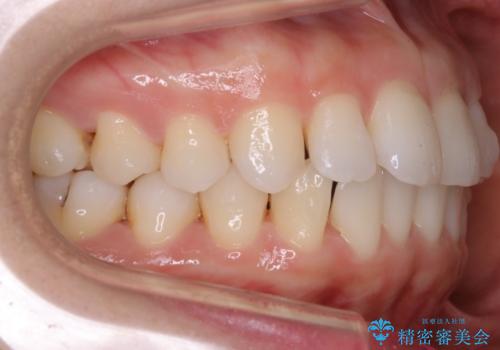

- 上下の前歯の細かいガタつきの治療をご希望されて来院されました。

奥歯部分にはガタつきや噛み合わせの問題などがほとんど見られず、前歯のガタつきも軽度だったため、インビザライン ライト パッケージでの部分矯正を行うこととなりました。

今回のケースでは奥歯の噛み合わせに問題がほぼみられなかったため、前歯の位置のみに焦点を当て部分矯正を行いました。

適応されるケースが限られるものの、適応であった場合の治療期間は全体矯正と比べると格段に短くなり、費用も抑えられます。